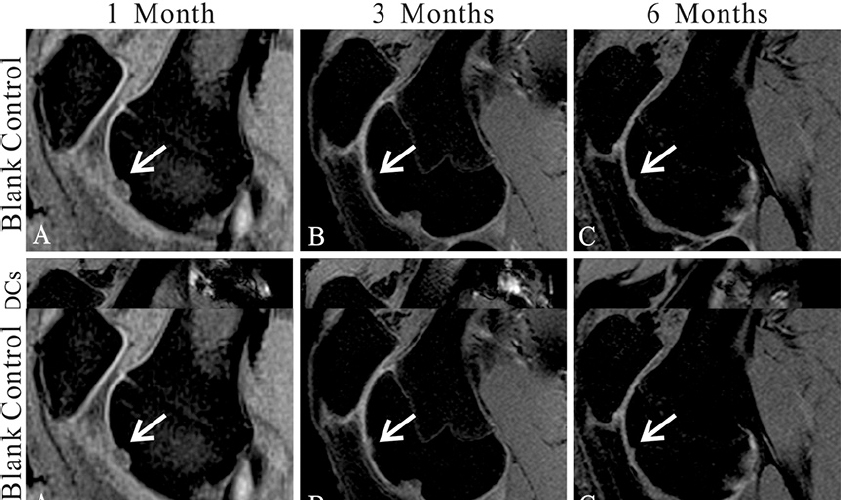

MRI showed no joint effusion or synovial hyperplasia in any tested knee. One month after surgery, MRI scans of the control group displayed a high signal intensity in the calcified layer and subchondral bone (Figure 1A), while MRI scans of the treatment group showed filling of the defect area benefiting from the implanted gel-cell complex and lower signal intensity than the surrounding cartilage (Figure 1D). Three months postoperativon, MRI scans or images of the control group detected inhomogeneous repair tissue with rough surfaces and thin thicknesses (Figure 1B). In contrast, the repaired tissue in the treatment group exhibited smooth surfaces and thicknesses similar to those of the adjacent cartilage (Figure 1E). Six months postoperation, the control group showed fibrillation and hypertrophy in the repaired tissue (Figure 1C), while the treatment group showed smooth surfaces and normal thickness (Figure 1F). The modified MOCART scores (Table 1) of the control and treatment groups were 10 ± 0 and 53.5 ± 4.7.4 at 1 month (n=10, p < 0.01), 42 ± 4.8.3 and 895. ± 5.99 at 3 months (n=10, p < 0.01), and 64 ± 6.99 and 96 ± 5.16 at 6 months (n=10, p < 0.01), respectively. These results clearly revealed the efficacy and significance of the one-step repair strategy.

Figure 1Magnetic resonance imaging (MRI) evaluation of the cartilage repair. (A-C) MR images show the tissue repair of the control group 1(A), 3(B), and 6(C) months postoperatively. (D-F) MR images show the tissue repair in the type II collagen (Col-II) + bone marrow-derived cell (BMDC) group 1(D), 3(E), and 6(F) months postoperatively. Sample sagittal MR images are of the tibiofemoral joint acquired using T2-weighted, fat-suppressed gradient echo. Arrows highlight the defects.